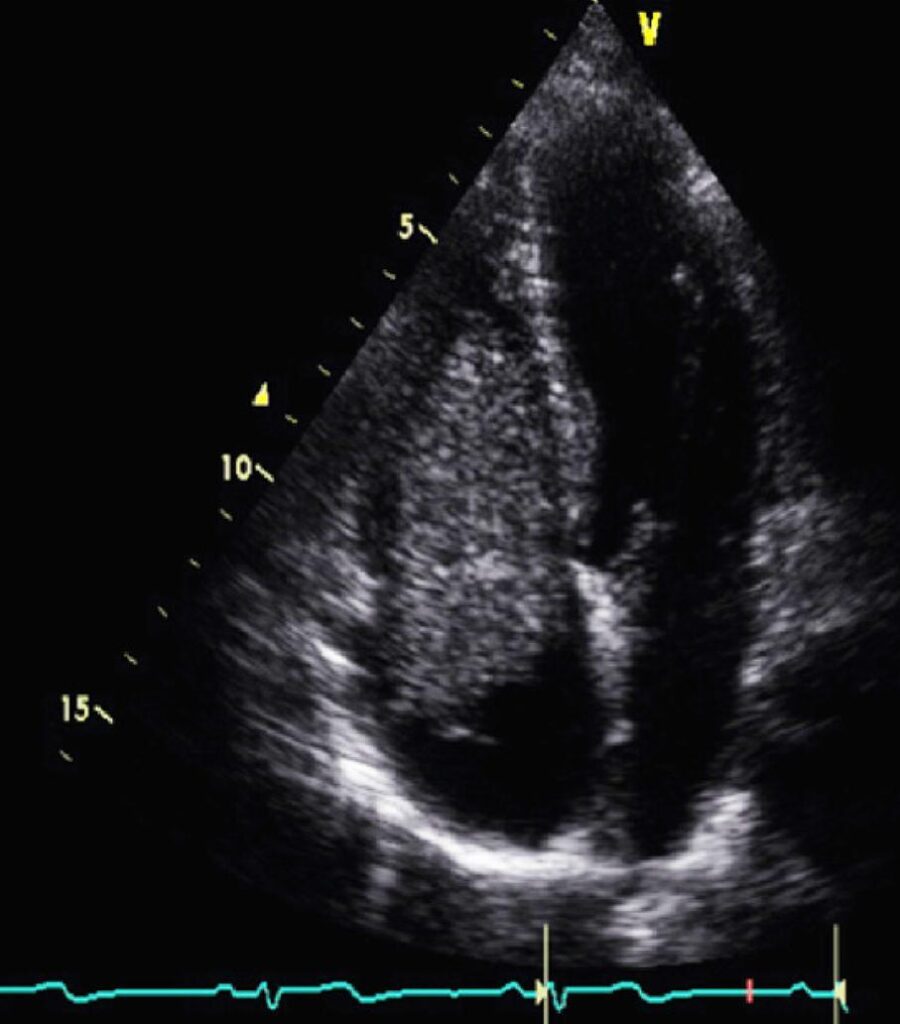

Third Recurrence of Cardiac Myxoma in a Carney Complex Patient

Primary cardiac tumors are an uncommon entity with an incidence of 0.3–0.7%. Most primary cardiac neoplasms are benign, with cardiac myxoma (CM) being the most prevalent type. Patients with CM may present symptoms due to embolic phenomena or intracardiac blood flow obstruction for which the treatment is surgical resection. Postoperative tumor recurrence occurs in up to 3% of cases; however, when myxomas are part of an underlying genetic syndrome, the recurrence rate can reach 22%. The main syndrome associated with this recurrence is the Carney complex (CNC). First described in 1985 by J. Aidan Carney, CNC is defined as an extremely rare autosomal dominant genetic syndrome with main clinical characteristics including skin pigmentation, heart myxomas, and endocrine neoplasms.